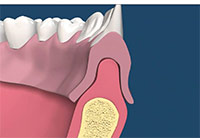

拔牙後處置

齒槽骨在牙齒拔除後的兩到三年,會面臨 40%-60%的萎縮,之後還會有每年 0.5%-1%後續的骨喪失,因此,一旦缺牙後若沒有儘快處理,患者日後將面臨齒槽骨萎縮引起的義齒製作困難及美觀問題。使用骨質增生膠原蛋白,來處理拔牙後的傷口。此材料適用的範圍不僅用於拔牙後傷口,所有顎骨中的病灶於手術後皆建議使用。牙科專用的3D電腦斷層攝影;與傳統醫療電腦斷層相比較,輻射劑量只有一般電腦斷層的1/50;切片厚度一般醫療電腦斷層是2.0公厘,牙科3D電腦斷層則只有0.1公厘,就診當天馬上拍攝電腦斷層,馬上獲得立體影像(圖01-04)